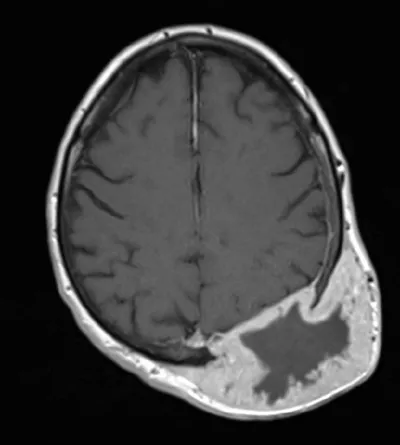

Метастаз рака почки у пациента 55 лет... 🦞😱